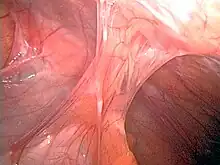

| Adhesions formed following appendectomy |